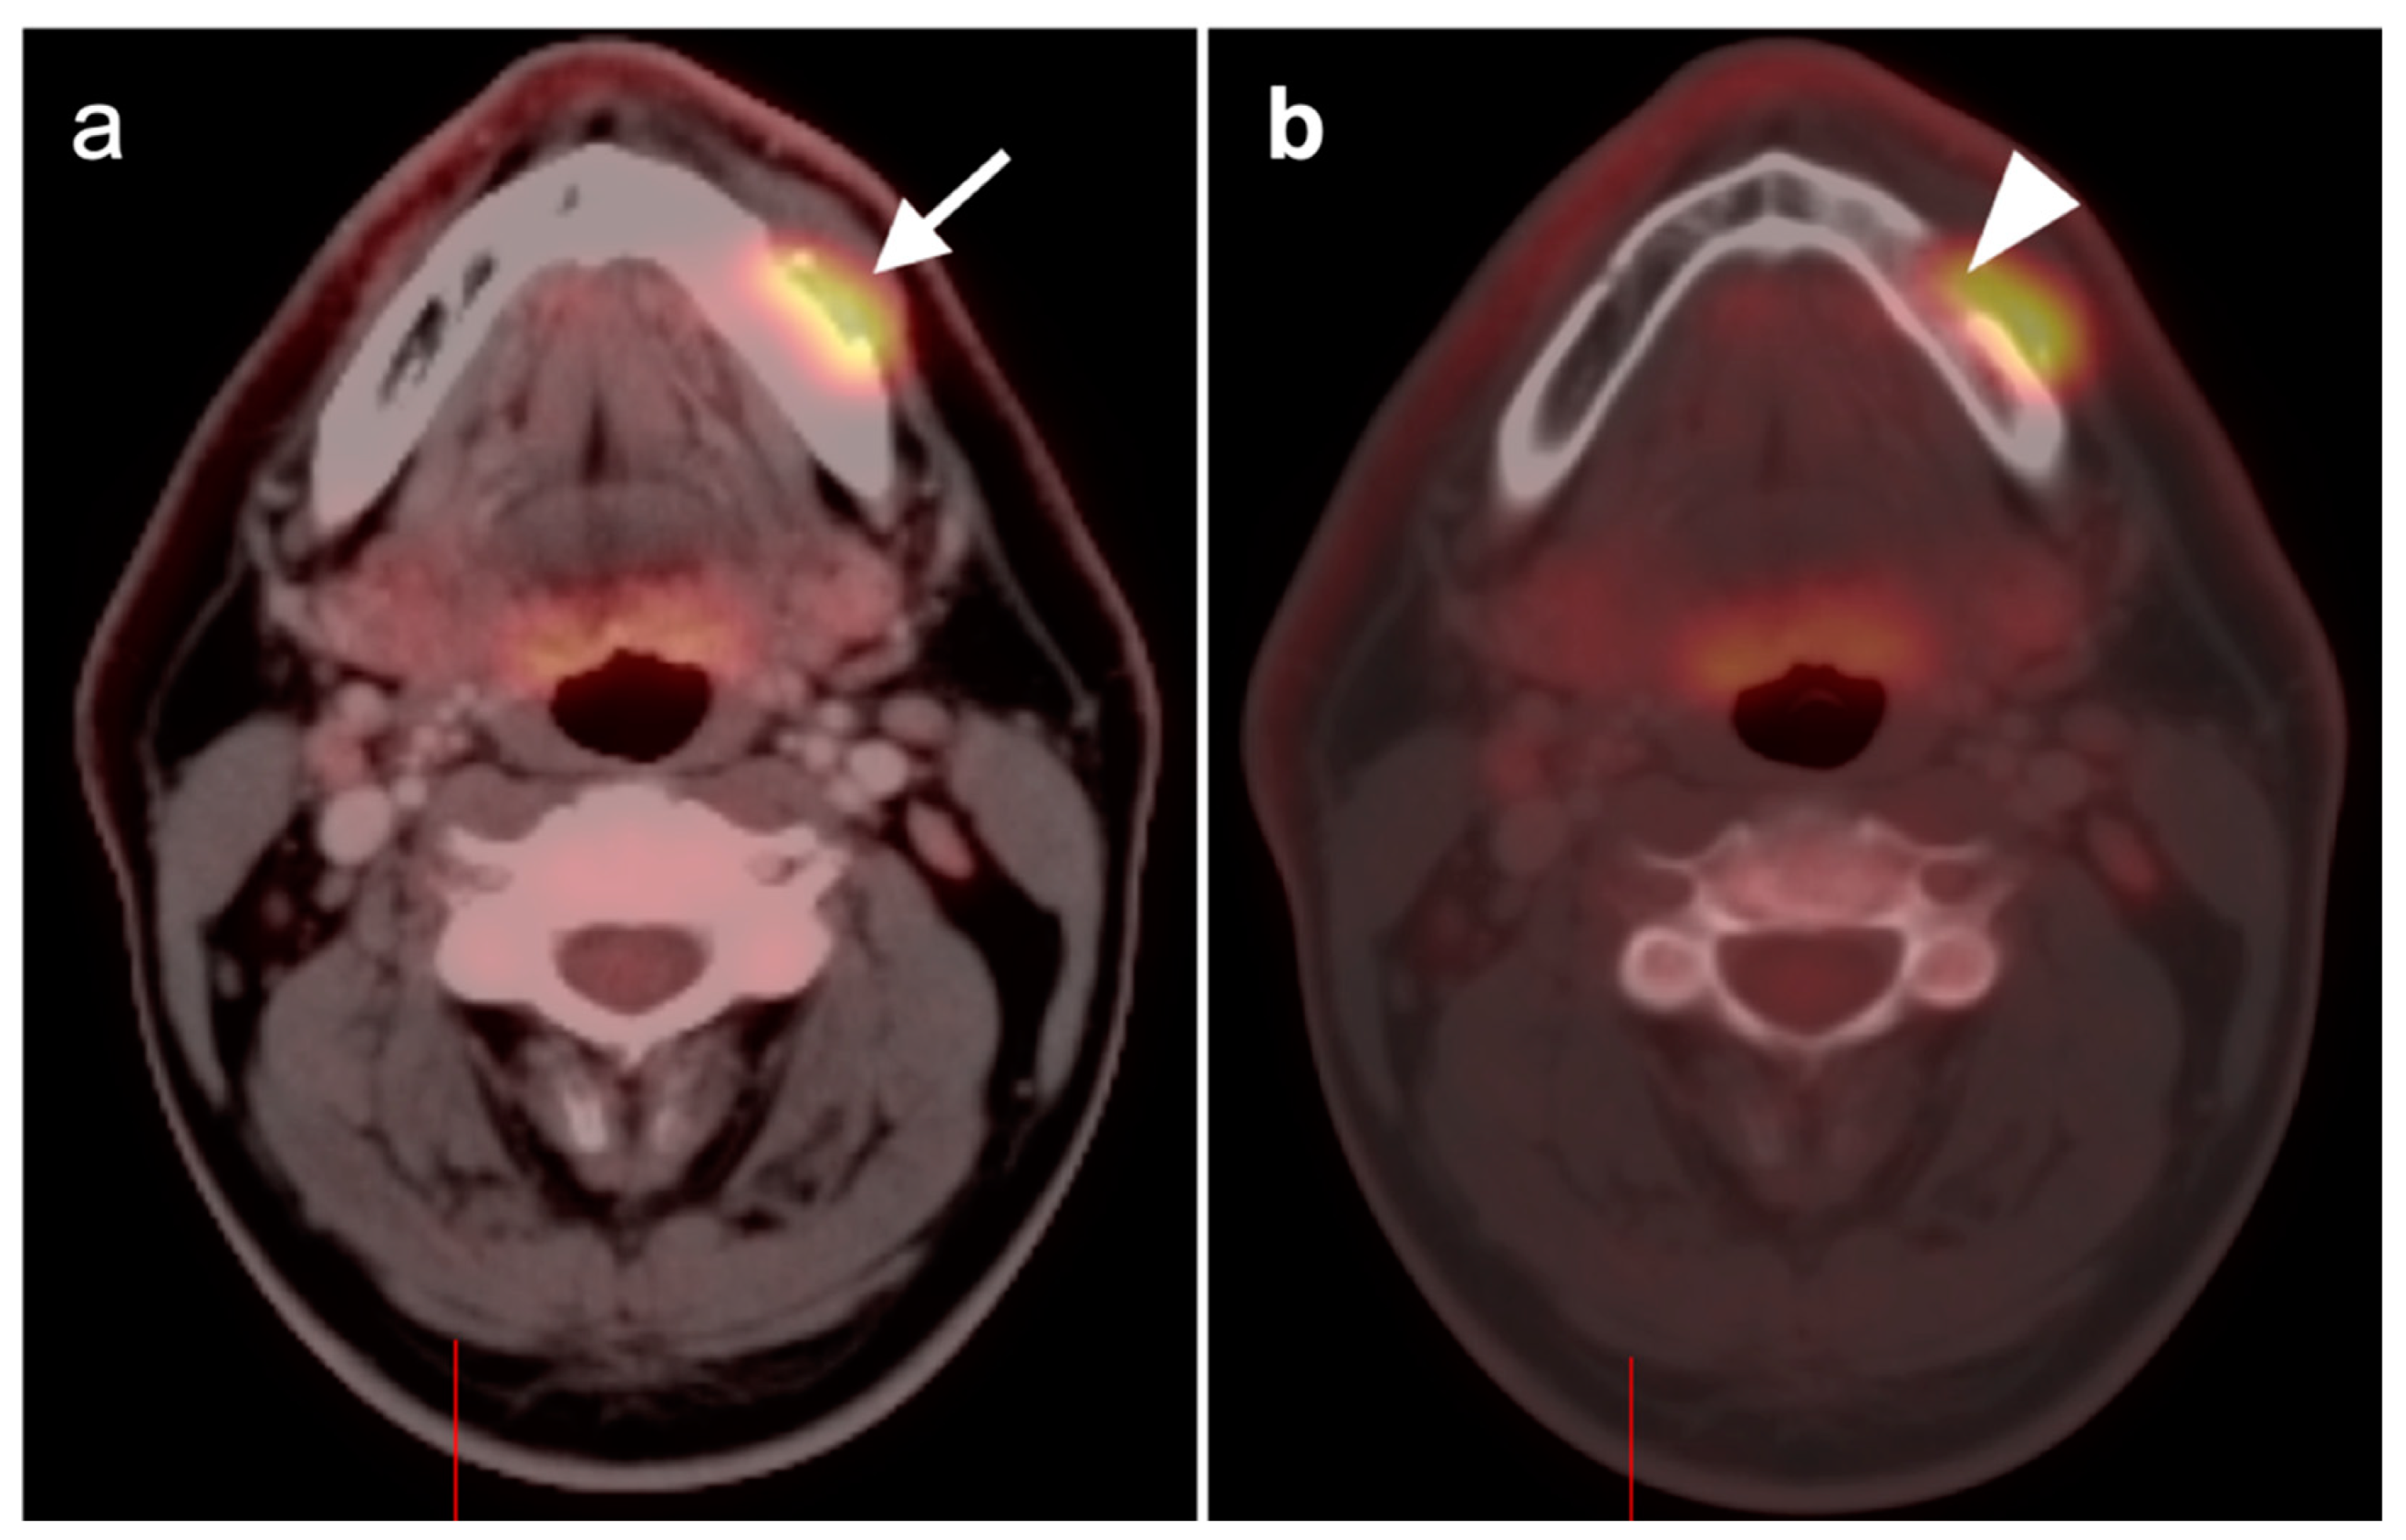

- Warthin tumor